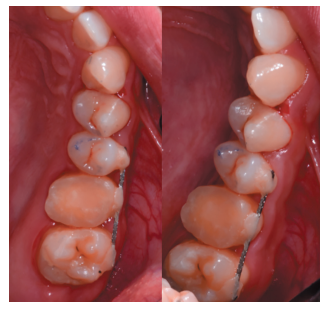

Caso clínico: se presenta el caso de un varón de 28 años, que acudió a consulta por la presencia de unos restos radiculares en localización de primer molar superior izquierdo. Se realizó un autotrasplante dental, siendo el diente donante el tercer molar superior izquierdo, que se trasplantó al alveolo del primer molar, mostrando buena evolución clínica y radiográfi ca.

Clinical case: a clinical case of a 28-yearold man is presented, who went to dental clinic for removal of left fi rst molar roots. An autotransplant was performed using left third molar as donor tooth, which was transplanted into fi rst molar alveolus, showing promising clinical and radiographic evolution.